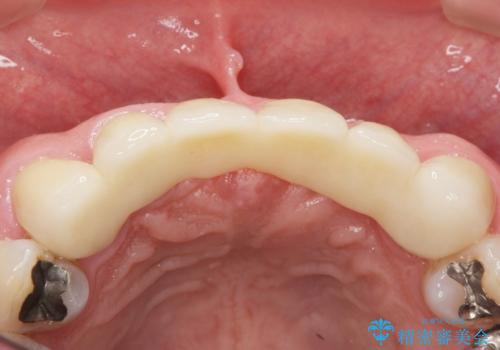

左上の側切歯(左上2)を抜去し、右上の側切歯(右上2)の再根管治療後、セラミックのブリッジによる補綴を行いました。

自然な仕上がりと咬み心地に大変ご満足頂けました。

「以前は出っ歯だったのにブリッジにしたことで歯並びもきれいになった!」と喜んで下さいました。

クラウンの種類:オールセラミッククラウン スタンダード